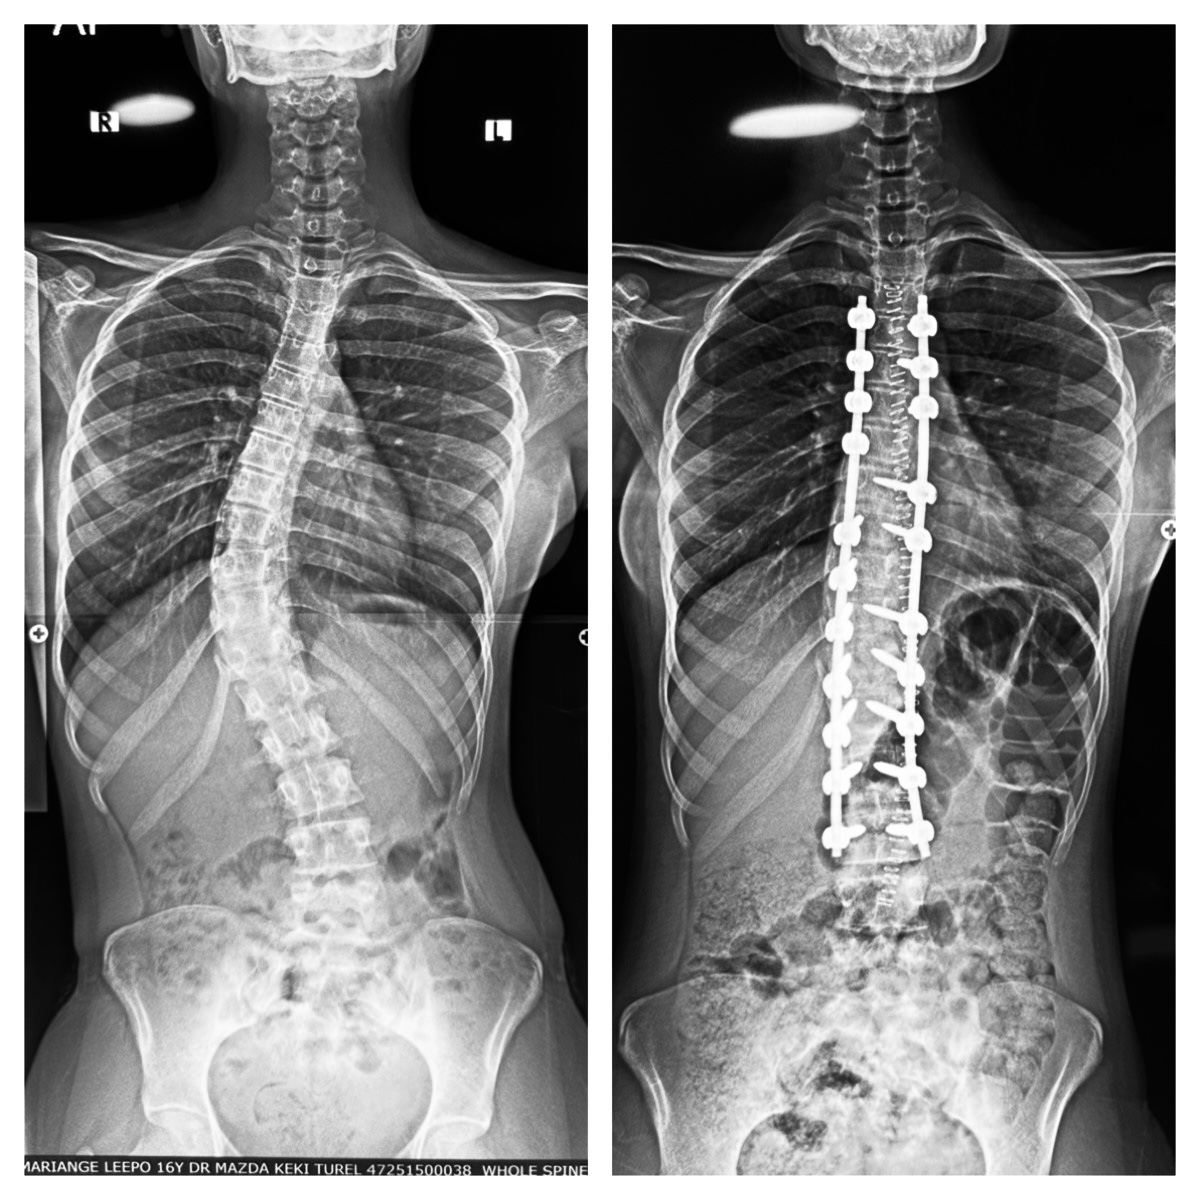

Her scans showed thoracolumbar scoliosis from T4 (the fourth thoracic vertebra) to L3 (the third lumbar vertebra) – 12 levels of deformity. That’s almost the whole length of her visible spine, from the base of her neck down to her lower back. It wasn’t going to straighten itself. Every scoliosis case is a learning curve – in geometry, patience, and humility.

On the morning of surgery, she was wheeled in looking smaller than she had in my clinic. Anaesthesia eased her to sleep. We turned her prone, carefully padded, her back exposed like a canvas waiting for correction. Through a midline incision, we exposed the spine from T4 to L3. Each vertebra was identified, and we placed screws with the precision of threading beads into a necklace. On one side of the curve, rods were fixed and gently rotated, gradually de-rotating the twisted vertebrae. On the other, the rod was fixed to balance the pull. The spine, which had curved like a bowstring, began to straighten under steady, controlled force.

Bit by bit, vertebra by vertebra, the arc dissolved. The correction was not just mechanical; it was aesthetic. A back that had once looked tilted now looked symmetrical. Shoulders levelled. A waistline returned. Even under drapes and monitors, you could sense the transformation. After tightening every screw, locking every rod, and checking alignment, we closed the incision in layers. What had been a crooked silhouette was now as straight as nature had originally intended.